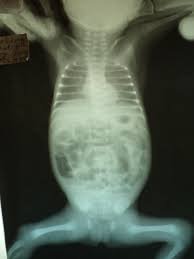

Лікар ніколи не діятиме наосліп. Спочатку ультразвук, ренген, можливо, РКТ. І буде ясно, де саме загвоздка.